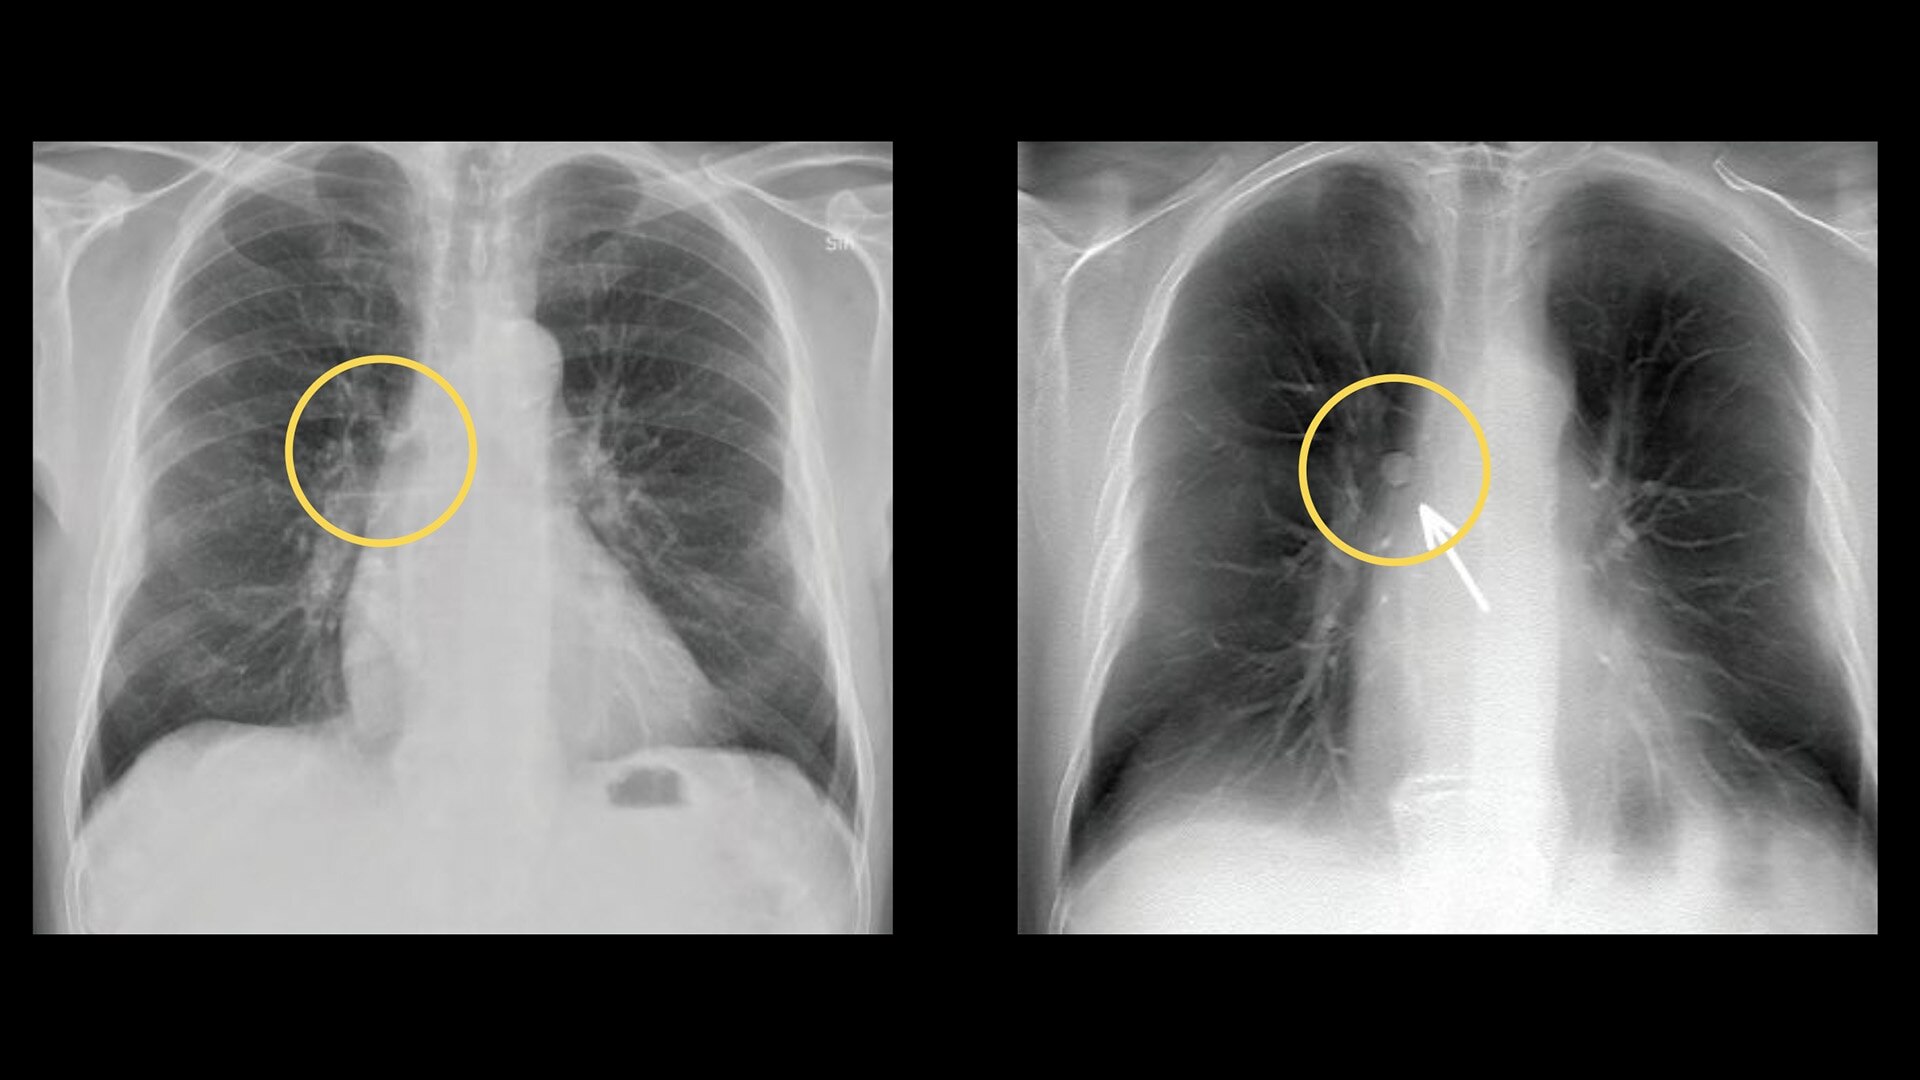

Lung nodule detection

Improve detectability of lung nodules and patient management15

VolumeRAD significantly increases detection sensitivity, enabling radiologists to confidently identify more lung nodules than 2-view chest X-ray. Radiologists also are significantly more accurate at correctly identifying cases requiring follow-up with VolumeRAD than with 2-view chest X-ray.15

• VolumeRAD is 3.6 times more sensitive than chest X-ray in detecting lung nodules 3 mm to 20 mm in diameter, without decreased specificity15

• VolumeRAD is 7.5 times more sensitive than chest X-ray in detecting lung nodules 4 mm to 6mm in diameter, without decreased specificity15